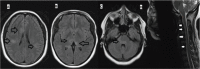

Stimulation of the immune response after vaccination can occasionally result in adverse effects, including demyelination of the central nervous system. The most common presentation of postvaccination demyelination is acute disseminated encephalomyelitis, but cases of optic neuritis, transverse myelitis, and multiple sclerosis relapses have been reported. More recently, an increasing number of postvaccination neuromyelitis optica spectrum disorder (NMOSD) cases have surfaced in the literature, especially in patients with aquaporin-4 antibodies. In this article, we report an unusual case of myelin oligodendrocyte glycoprotein antibody-related NMOSD after the receipt of multiple vaccines in a first-trimester pregnant woman from Africa. We review the reported cases of postvaccination demyelination in the past decade, with a focus on the relationship between NMOSD and vaccination in patients with aquaporin-4 or myelin oligodendrocyte glycoprotein antibodies. Finally, we discuss the clinical relevance of the present case and similar reported cases as it relates to patient care in the neuroimmunology clinic and identify potential areas for future research.